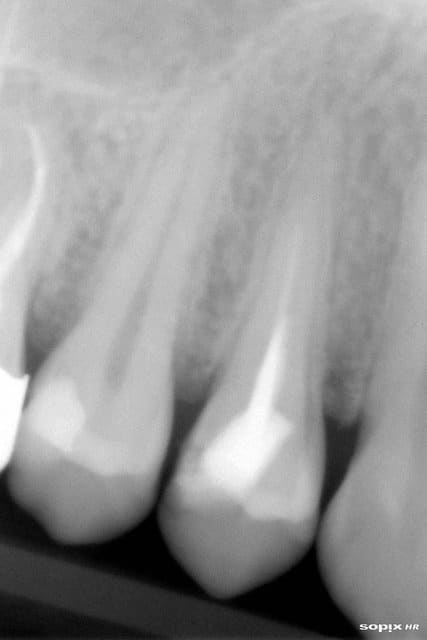

2 retraitements endo sur 45 46.